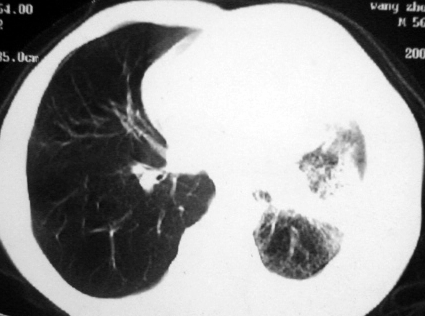

男,54岁,咳嗽,气喘半年,胸痛一月.

血性胸水

左侧胸腔积液 斜裂积液 心包积液 左肺不张 考虑左肺ca并胸膜心包转移。

支持左肺下叶中心型肺癌(累及舌叶)伴阻塞性肺炎、膨胀不全、胸腔积液、心包少量积液。

左肺下叶中心型肺癌,伴阻塞性肺炎、左胸腔积液、心包少量积液。

考虑左下叶中心型肺癌,伴阻塞性肺炎,左胸腔积液,心包积液,建议纤支镜检查